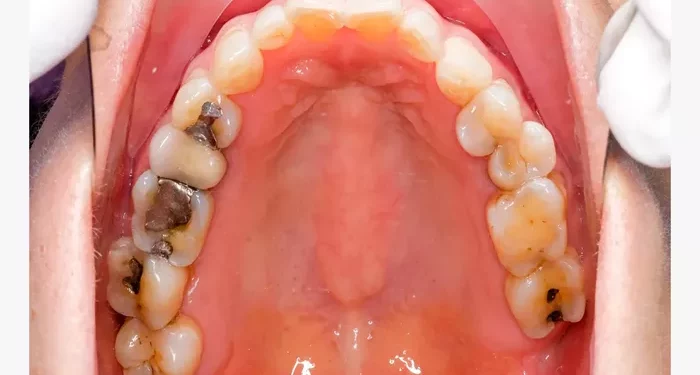

Cavities are small holes that form in the enamel of your teeth. They are caused by the demineralization of tooth structure due to acids produced by bacteria in the mouth. Poor oral hygiene, a diet high in sugars, and certain medical conditions can contribute to cavity formation. Recognizing the early signs of cavities is crucial for timely treatment.

Amalgam Fillings

Amalgam is a mixture of metals, including silver, mercury, and tin. These fillings are known for their strength and durability. They are often used in back teeth where chewing pressure is greater. However, they are not as aesthetically pleasing as other options.